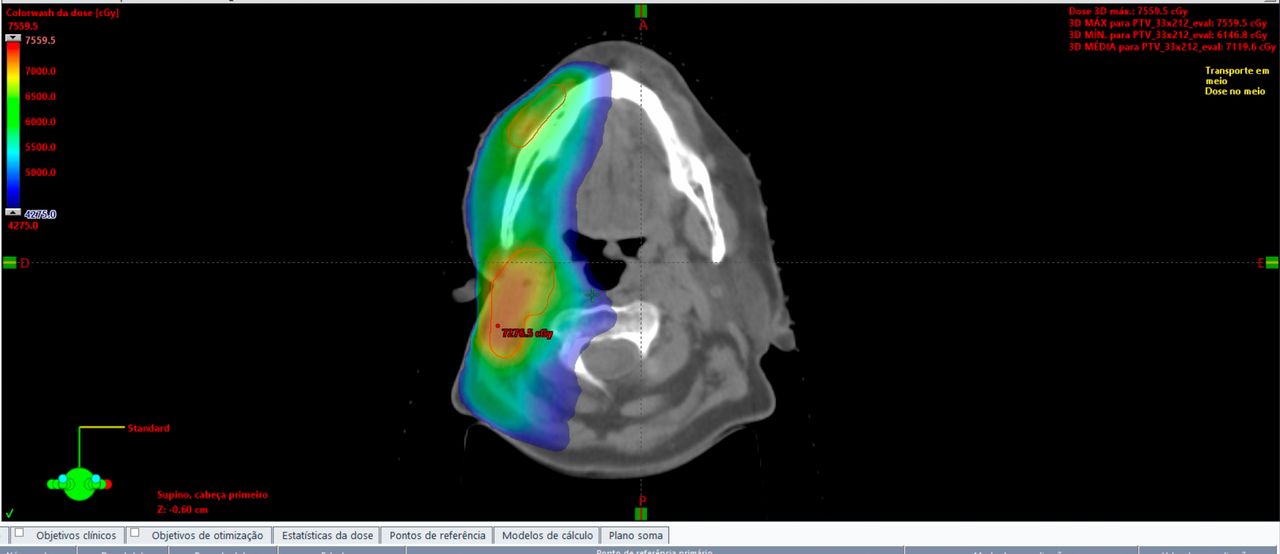

Tem interesse amplo em radioterapia, com familiaridade com diversas técnicas: Braquiterapia, Betaterapia, RT-3D, IMRT, IGRT, Radiocirurgia e SBRT. Tanto para o uso em tumores benignos e queloides, quanto, para tumores malignos. Tem interesse em de formas de minimizar toxicidades relacionadas à radioterapia e ampliação do cuidado em dor.

No tratamento oncológico é reconhecido pela sua capacidade técnica e qualificação, tem interesse em cânceres do Trato Gênito Urinário, principalmente, Câncer de Próstata e Cânceres Ginecológicos, tumores da Mama e do Pulmão. Atuou em São Paulo/SP, nos Hospitais: Beneficência Portuguesa, Santa Catarina - Paulista e Santa Paula e, ainda, como coordenador médico do Hospital Vitória - Santos/SP.